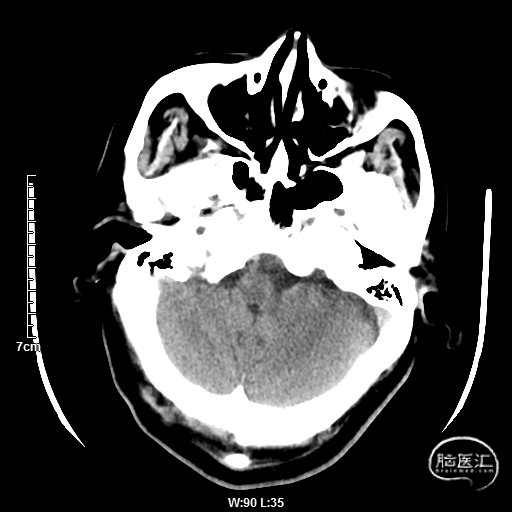

颅脑CT:未见明显缺血/出血病灶。

CTA提示:右侧椎动脉纤细,左侧椎动脉V1、V4段纤细。

MRI提示小脑缺血性改变。

术后CT:未见明显脑出血,双侧小脑低密度影。

术后CTA:Bridge药物支架形态良好,前向血流良好。

术后半年CTA:Bridge支架形态及贴壁良好,前向血流正常。